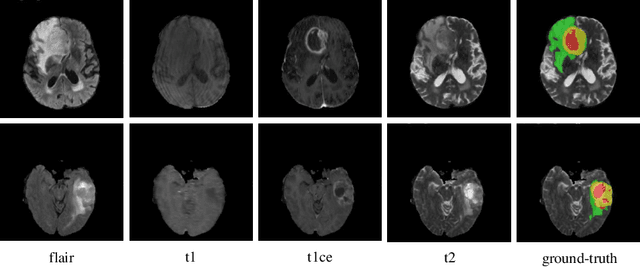

Abstract:In our previous work, $i.e.$, HNF-Net, high-resolution feature representation and light-weight non-local self-attention mechanism are exploited for brain tumor segmentation using multi-modal MR imaging. In this paper, we extend our HNF-Net to HNF-Netv2 by adding inter-scale and intra-scale semantic discrimination enhancing blocks to further exploit global semantic discrimination for the obtained high-resolution features. We trained and evaluated our HNF-Netv2 on the multi-modal Brain Tumor Segmentation Challenge (BraTS) 2021 dataset. The result on the test set shows that our HNF-Netv2 achieved the average Dice scores of 0.878514, 0.872985, and 0.924919, as well as the Hausdorff distances ($95\%$) of 8.9184, 16.2530, and 4.4895 for the enhancing tumor, tumor core, and whole tumor, respectively. Our method won the RSNA 2021 Brain Tumor AI Challenge Prize (Segmentation Task), which ranks 8th out of all 1250 submitted results.